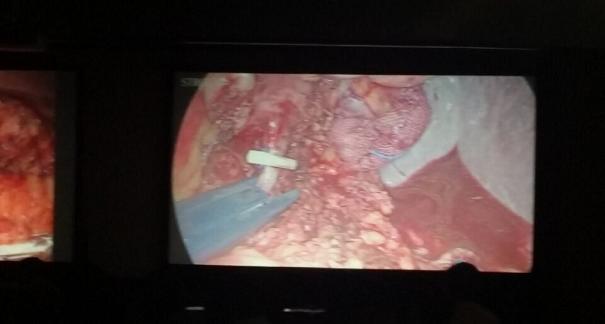

2015年10月23-25日,河北省醫(yī)學(xué)會(huì)肝膽外科學(xué)術(shù)年會(huì)在河北省石家莊市頤園賓館隆重召開。本次學(xué)術(shù)會(huì)議河北省醫(yī)學(xué)會(huì)特邀了北京301總院的胡明根教授、天津第一中心醫(yī)院的張雅敏教授、山西醫(yī)大醫(yī)院的趙浩亮、河北醫(yī)科大學(xué)第二醫(yī)院劉建華教授等國(guó)內(nèi)知名專家參會(huì)。參加會(huì)議的醫(yī)院達(dá)100余家,近300名肝膽外科的臨床專家和一線醫(yī)生們親臨會(huì)場(chǎng),在此進(jìn)行廣泛的學(xué)術(shù)交流。25號(hào)全天會(huì)議安排了五臺(tái)手術(shù)視頻演示,全體參會(huì)人員進(jìn)行觀摩,并實(shí)時(shí)提問,進(jìn)行手術(shù)交流。演示手術(shù)包括腹腔鏡胰、十二指腸切除術(shù)、腹腔鏡左、右半肝切除術(shù)、腹腔鏡門脈高壓癥的治療、兩鏡或三鏡聯(lián)合膽石癥的治療、開腹胰、十二指腸切除術(shù)、手術(shù)演示中多次使用了我公司產(chǎn)品速豐(可吸收止血結(jié)扎夾),產(chǎn)品使用滿意度受到專家們的一致好評(píng)。